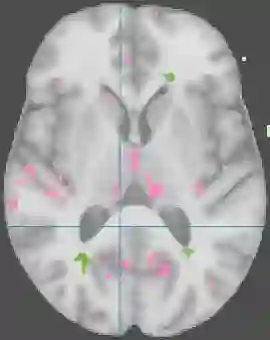

Brain pathologies often manifest as partial or complete loss of tissue. The goal of many neuroimaging studies is to capture the location and amount of tissue changes with respect to a clinical variable of interest, such as disease progression. Morphometric analysis approaches capture local differences in the distribution of tissue or other quantities of interest in relation to a clinical variable. We propose to augment morphometric analysis with an additional feature extraction step based on unbalanced optimal transport. The optimal transport feature extraction step increases statistical power for pathologies that cause spatially dispersed tissue loss, minimizes sensitivity to shifts due to spatial misalignment or differences in brain topology, and separates changes due to volume differences from changes due to tissue location. We demonstrate the proposed optimal transport feature extraction step in the context of a volumetric morphometric analysis of the OASIS-1 study for Alzheimer's disease. The results demonstrate that the proposed approach can identify tissue changes and differences that are not otherwise measurable.